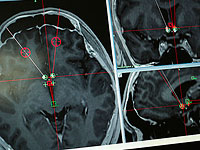

Клиническое исследование: новое лечение уничтожает раковые опухоли головы и шеи

В ходе исследования было установлено, что коктейль иммунотерапевтических препаратов действует на иммунную систему пациентов с тем, чтобы уничтожать их собственные раковые клетки, и дает "положительную тенденцию в выживании".